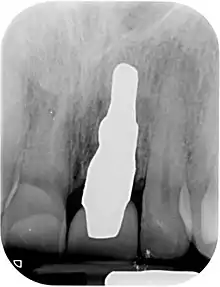

X-ray of root analogue dental implant single rooted right lower second premolar